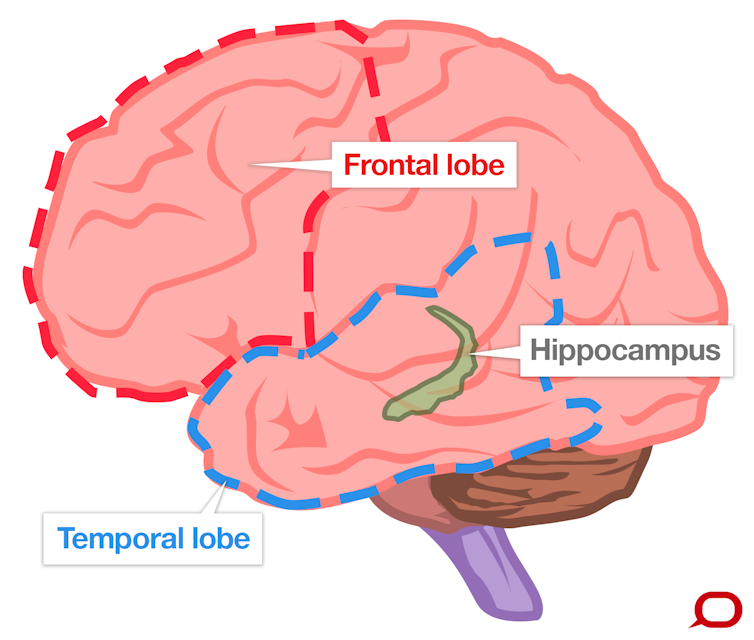

Dementia: What Part of the Brain is Under Attack?

DSA Blog on Dementia and Brain Health: Identifying Frontotemporal Dementia